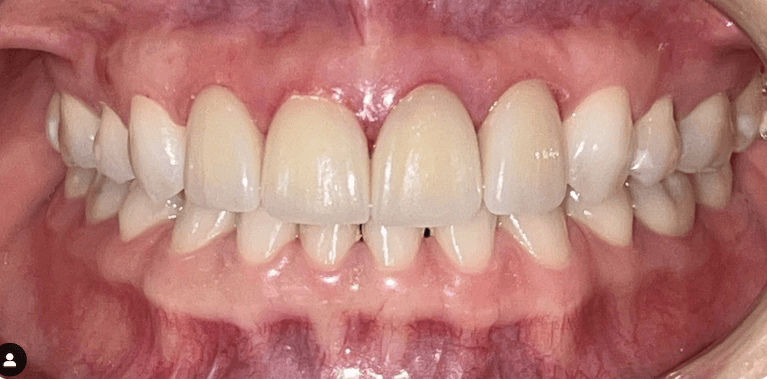

White spot treatment with Icon and mild spacing correction with Invisalign(5weeks only)

Sometimes it’s the little things that matter the most.